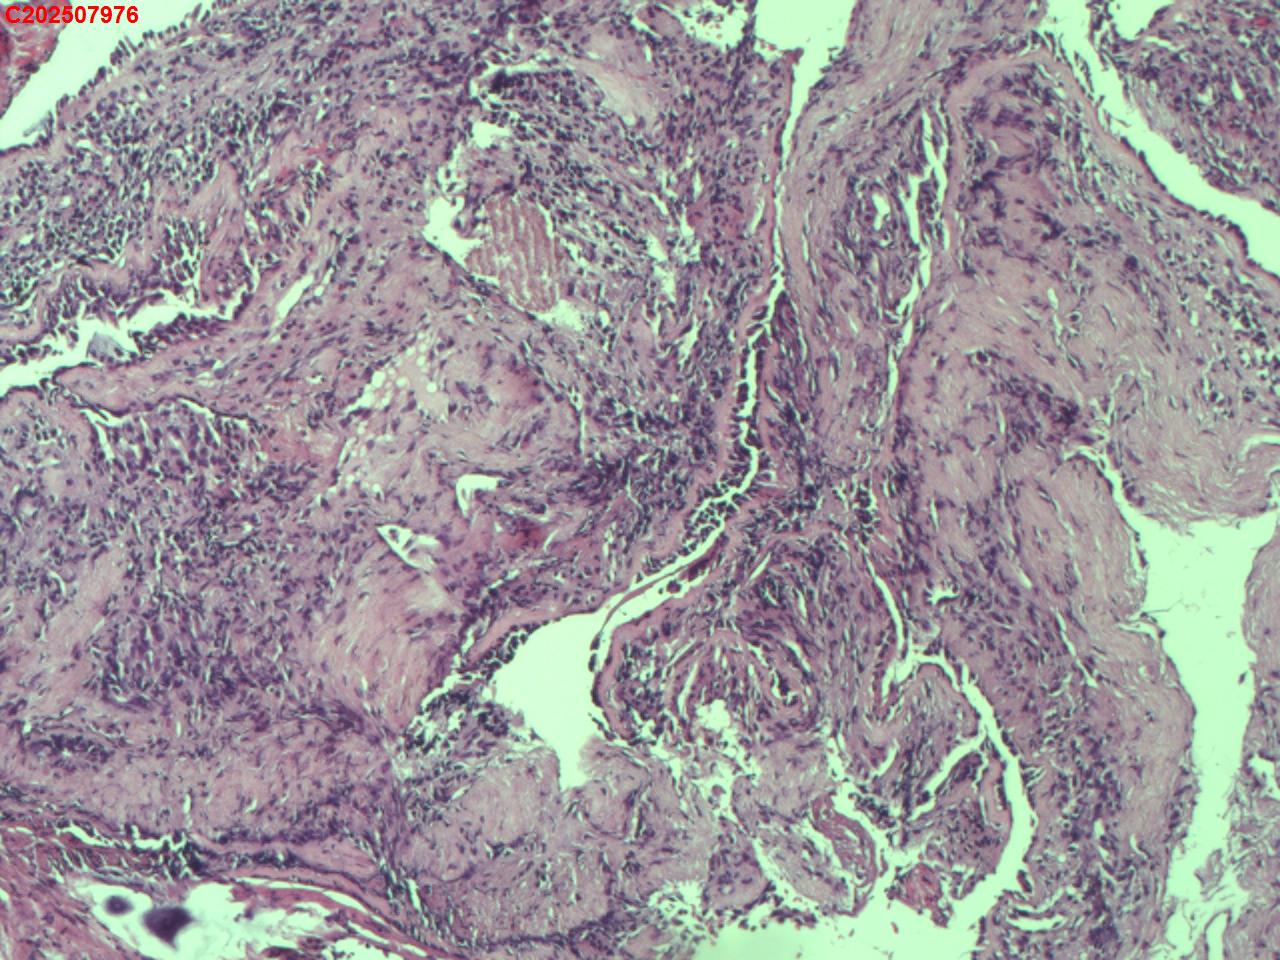

右肺上叶开口处 气管镜咬检

右肺上叶开口上缘处可见肉芽增生,予咬检。

图2

感觉:炎性纤维组织增生